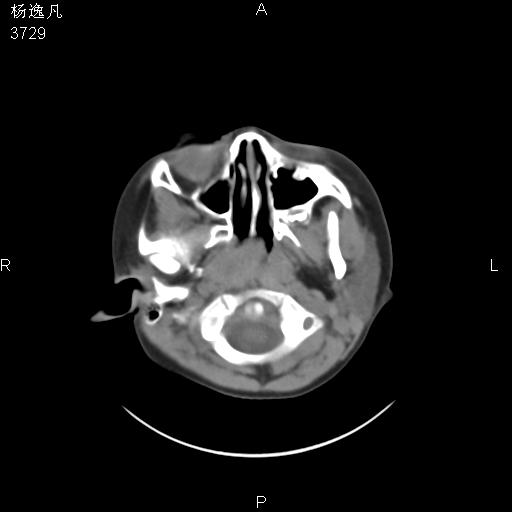

男性,5岁,面部受外伤,余无特殊

软组织窗

1、右面部及颞部软组织肿胀。

2、腺样体肥大。

头颅ct平扫未见明确外伤性征象,右侧面部及颞部软组织肿胀,后鼻腔软组织影增大,增厚,鼻咽顶部变窄,考虑鼻咽腺样体增值肥厚。